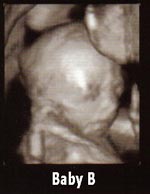

Yep - Baby A is me, Baby B is DH Image Attachment(s):

did anyone try to guess which one was what sex by the pics? I have to tell ya my guess would be A- Girl B-Boy . They dont look like the same sex to me. DO you know yet?

LOL...totally! I definately think Baby B's a boy

Yeah he kind of looks like a little old man right?